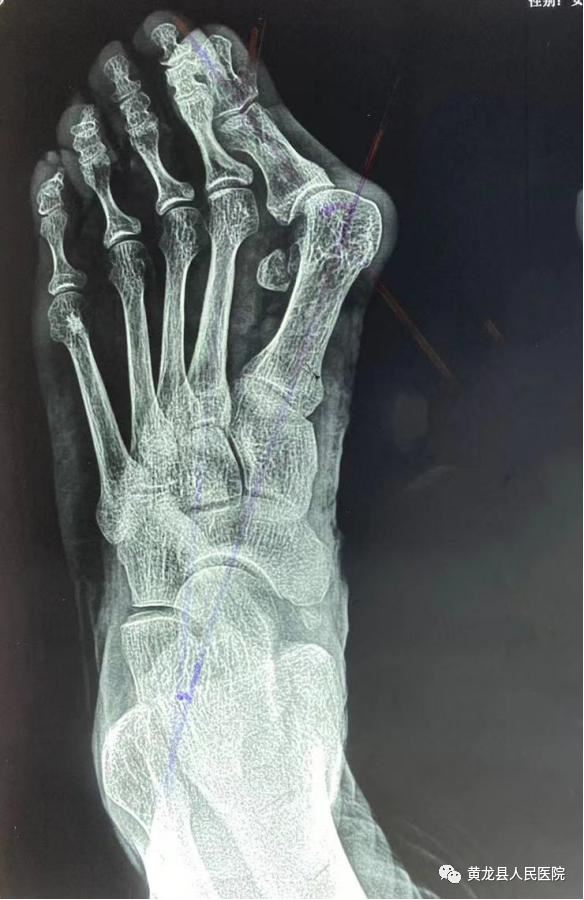

术前X线 术后X线

以上大家看到的影像图片,是一位58岁的女性患者,由于双足踇趾畸形3年余,剧烈疼痛导致穿鞋及活动严重受限。3年前,患者出现双足踇趾向外偏斜,当时畸形不严重,踇趾内侧稍红肿,未予诊治,1年前右足踇趾内侧疼痛明显,活动后疼痛加剧,只有休息后才能稍缓解。患者于1月11日来到黄龙县人民医院外科就诊,经过外科主任方继荣详细询问病史及仔细体格检查后,将患者收治入院治疗。结合患者病情,多方考虑需手术效果最佳,告知患者及家属得到同意。术前,考虑到患者年龄稍微偏大,手术有风险。方继荣带领外科医师对手术风险做了充分评估,对手术方案进行多次讨论,制定了详细周密的手术方案,最终于1月14日上午顺利进行手术。方继荣主刀,在外科医师及手麻科积极配合下,仅用不到1小时,手术顺利完成,达到了术前预期效果,经过手术治疗后,患者脚部成功恢复了美丽的外观,患者及家属对手术效果表示非常满意,向医务人员多次表示感谢。